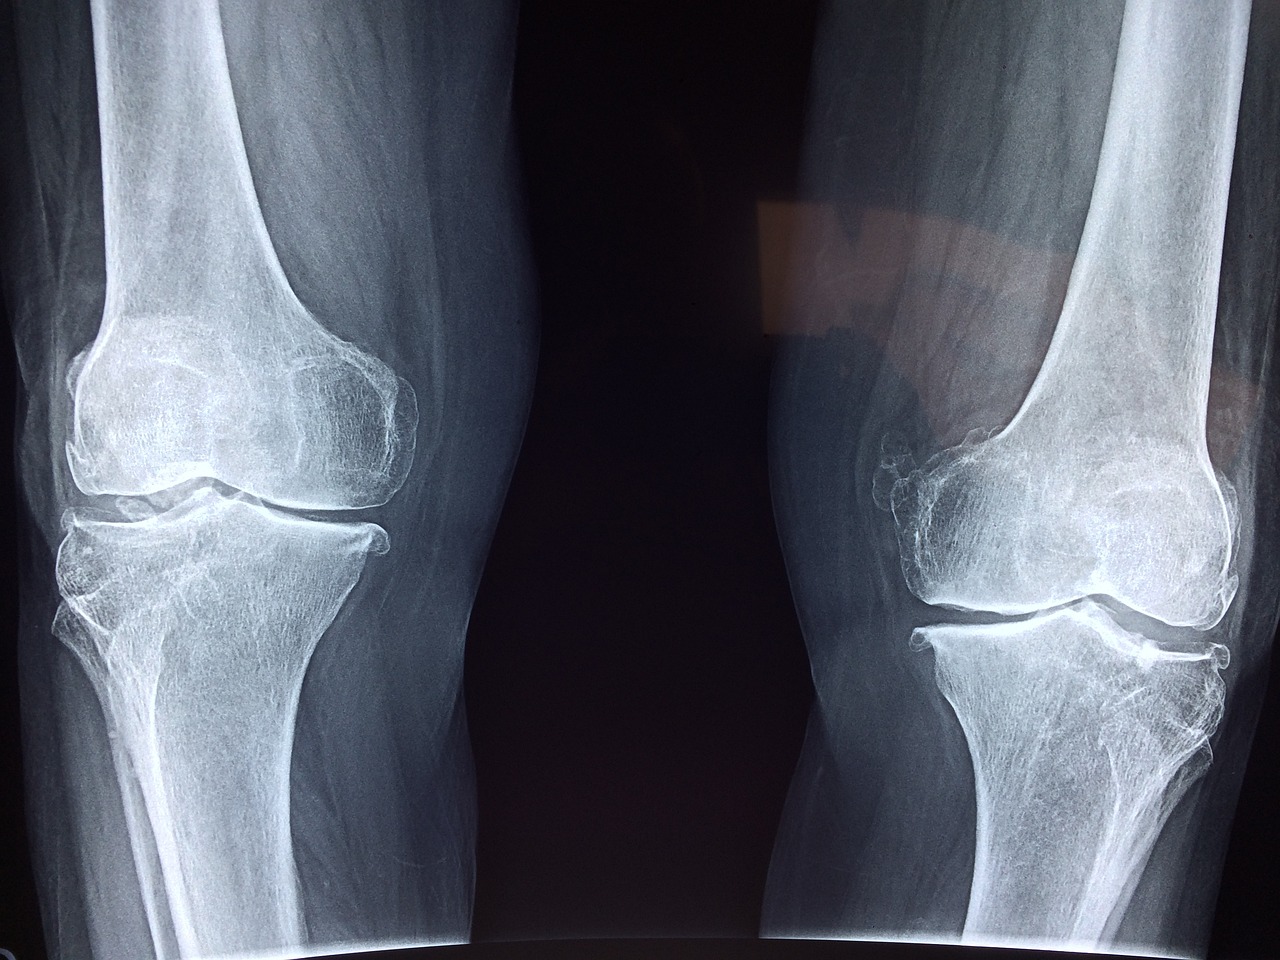

- MRI 검사를 통해 연골 손상 정도를 정밀하게 확인해야 합니다. X-ray만으로 치료를 결정하는 경우 부정확할 수 있습니다.